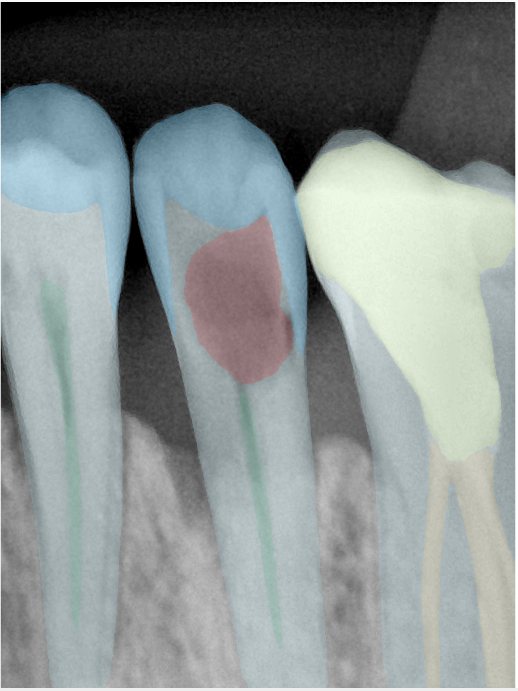

CR/DR 牙齿分割阶段记录

当前进展

- 完成了 CR/DR 牙齿相关分割训练

- 当前结果已经达到阶段预期,但仍有细节问题需要继续处理

相关测试

遇到的问题

- 训练过程中出现过 mask 下移问题

- 部分结果会出现 box 填充异常

- mask 边缘仍然有比较明显的锯齿感